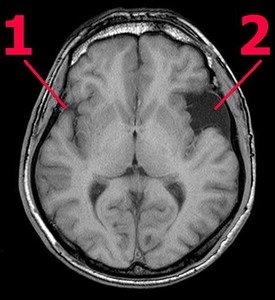

Киста головного мозга — это полостное образование, которое может возникать по различным причинам, включая травмы, инфекции или генетические факторы. Многие люди, столкнувшиеся с этой проблемой, отмечают, что первоначально не испытывают никаких симптомов, и киста может быть обнаружена случайно при проведении МРТ. Однако со временем, в зависимости от размера и расположения, киста может вызывать головные боли, нарушения зрения или даже проблемы с координацией.

Обсуждая последствия, пациенты часто выражают опасения по поводу возможных осложнений, таких как повышение внутричерепного давления или сдавление окружающих тканей. Важно отметить, что не все кисты требуют лечения; некоторые могут оставаться стабильными на протяжении многих лет. Тем не менее, регулярное наблюдение и консультации с врачом играют ключевую роль в управлении состоянием и предотвращении потенциальных рисков.